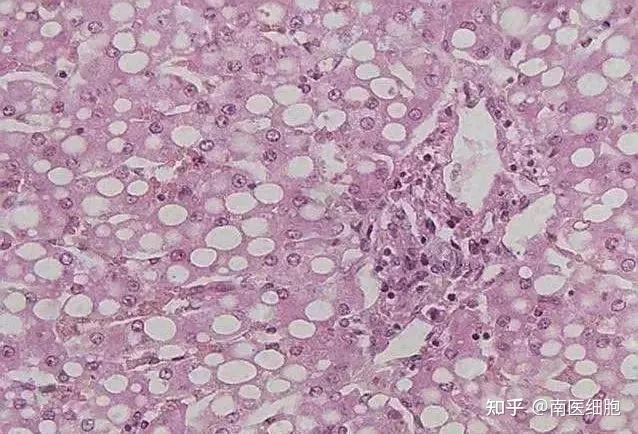

——身体有过多脂肪的人容易得脂肪肝,而试图通过药物或节食来减肥的人也会有得脂肪肝的概率,因为这些行为会阻断营养吸收,致使体内蛋白质缺乏,低密度脂蛋白合成减少,肝脏转运出现障碍,脂肪就会在肝内堆积,长久不得排出就会引起肝炎。